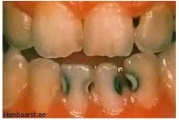

Krooniline parodontiit

ANUG (äge nekrotiseeruv haavandiline gingiviit/parodontiit)

Parodontiit